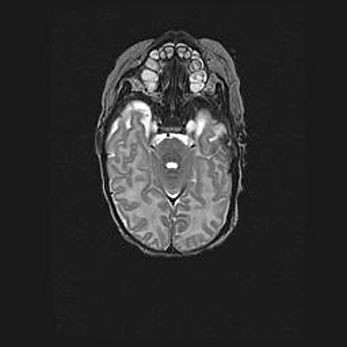

Неполная лизэнцефалия (пахигирия). Открытая гидроцефалия.

Возраст: 17 дней

Вес: 3110 г

Пол: мужской

Окружность головы: 33,5 см

Срок гестации: 35-36 недель

Лизэнцефалия—недоразвитие корковой пластинки и мозговых извилин в результате нарушения миграции нейронов коры. Поверхность мозговых полушарий гладкая. Микроскопически выявляется отсутствие нормальных слоев коры и скопление групп нейронов в подкорковом белом веществе.

Пахигирия—уменьшение числа вторичных извилин. В пораженном полушарии нервные клетки образуют толстый недифференцированный слой с неправильно расположенными нервными волокнами и группами гетеротопных клеток. Нервные клетки незрелые. Белое вещество истончено. При этом нередко аномально развит корково-спинномозговой путь.